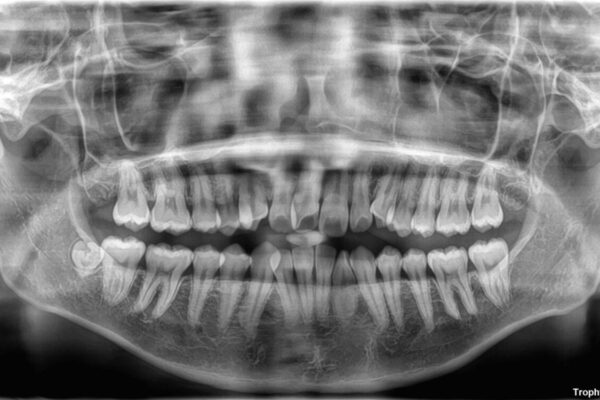

治療計画

「前歯のデコボコ(叢生)をきれいに整えたい」とのことでご来院されました。

マウスピース矯正も検討されていましたが、「装着時間の自己管理が難しそう」「なるべく早く治療を終えたい」とのご希望から、ワイヤー矯正を選択されました。

目立ちにくさと費用のバランスを考慮し、プラスチックブラケット+メタルワイヤーを採用。日常生活でも装置の存在感を気にせずお過ごしいただけます。

患者様の協力もあり、およそ1年間で治療を完了。スムーズな歯の移動を実現しました。

上下の正中(真ん中のライン)もずれることなく、バランスの取れた美しい歯並びに。笑顔に自信を持てる仕上がりとなりました。